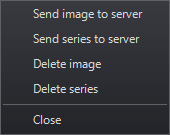

A Szerkesztési és Lelet jogosultságokkal rendelkező felhasználók feltölthetik az exportált MPR képeket és sorozatokat a kiszolgálóra, így más felhasználók is hozzáférhetnek.

Amint egy exportált képet elmentett a kiszolgálóra, azt kulcsképként csatolhatja egy lelethez.